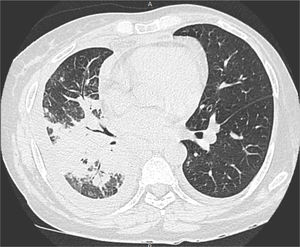

The biopsy fragment culture, general biochemical analyses, blood cultures, and serology, including anti-HIV, and anti-Paracoccidioides, were normal or negative. The chest CT (Fig. 4) showed coalescent pulmonary consolidations, septal thickening and excavated lesions in the lower portions and lymph node enlargement, compatible with the diagnosis of paracoccidioidomycosis due to the likely reactivation of a quiescent pulmonary focus.8